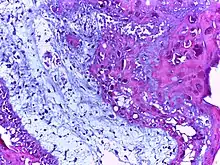

![]() | Foreign body granuloma | Granulomatous reaction to keratin characterized by foreign body giant cells and chronic inflammatory cells. | Category: Histopathology of foreign body granuloma | Foreign body granuloma, silicone granuloma |